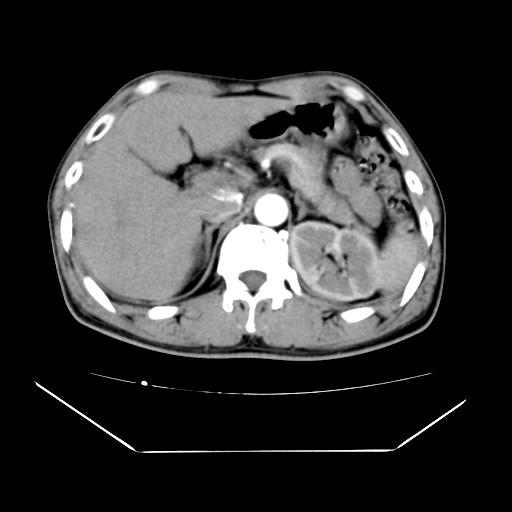

男性,55岁,外院体检afp明显升高,但b超未发现异常,否认乙肝病史。来我院ct增强。有延时扫描。

左肾囊肿.右肺中叶内侧段钙化灶.慢性胆囊炎.

延时扫描完全充填,血管瘤

肝脏右叶动脉期可见低密度影,至延迟期被充填,考虑血管瘤可能性大。

不排除肝右叶肝癌可能。

这个不是肝右静脉吗,这么大的病灶b超不可能发现不了吧

如果这个是癌灶的话则下腔静脉有瘤栓可能

肝6段血管瘤

血管瘤可能性大。